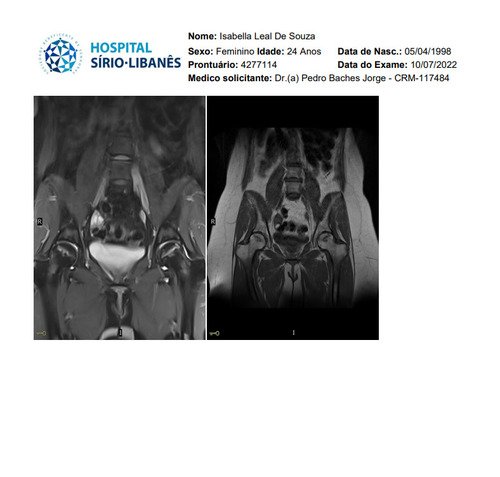

Não sei por onde começar porque e uma história longa e vou tentar resumir, fiquei meses tentando descobrir que eu tinha fibromialgia, porém eu não tenho só isso, tive edemas na coluna, problemas na lombar, e até derrame pleural eu tive, eu pago aluguel que e 1300 mais o condominio que e 450, fora que eu me planejei e não tenho familia pra apoiar entre outras coisas, quando me mudei e planejei pra poder ter o proprio ape eu não sabia que do nada iria ficar doente, em março de 2023 eu pego as chaves mas até la ta dificil, fiz emprestimo e várias outras coisas porque só a medicação de durogesic que eu uso e restiva um a caixa e 650 e o outro 300, podem pesquisar, após um procedimento na lombar cirurgico pra tentar aliviar a dor descobri uma necrose asseptica na cabeça dos dois femur, com risco de ter que colocar uma protese, até pouco tempo estava de muleta, só podia ficar sentada, e mesmo a dor e muito forte, eu ainda não sei a tal outra doença que eu tenho, já aconteceu de eu entrar na emergência e ficar na UTI, tive mais de 10 internações no hospital e não e mentira, minha maior luta e conseguir tratar essa necrose, poder voltar a praticar esportes, sei que tem gente que precisa muito mais mas eu cheguei no meu limite e to até com um aluguel atrasado, todas as coisas que eu estiver pagando eu vou colocar nota fiscal porque eu não to aqui pra fazer ninguém de trouxa, vou colocar exame, fotos de internação entre outras coisas que posso, porque tem algumas que não posso devido porque não quero imagem negativa para local de trabalho (e aonde eu trabalho eles estão me ajudando e muito), e de acordo de como for funcionando a vakinha eu vou vendo se aumento, eu só queria me livrar dessas contas sufocantes primeiro, e agora os médicos estão lutando pra descobrir a outra doença que tenho além dessa da necrose que ta me deixando muito mal e que a fibromialgia atrapalha a descobrir, sei que e chato porque já pedi ajuda 2 vezes, mas conversei com amigos e infelizmente eu não tenho outra opção a não ser pedir ajuda, vou colocar exame de tudo etc, o valor até de emprestimos que estou devendo e tudo mais, e podem me perguntar qualquer coisa que eu respondo e claro, vou postar nota fiscal pra provar que to pagando o que to mostrando, eu to no meu limite, e não e fácil, eu ficava 3 dias seguidos sem conseguir dormir e os médicos não conseguiam descobrir e ainda sigo firme no tratamento porque vou encontrar uma resposta e não posso desistir do tratamento, eu poderia fazer um textao aqui mas com poucas palavras já consigo ser direta, obrigada a quem ajuda e continua me apoiando desde o começo e pra quem não gosta e não acredita e só não ajudar, ninguém vai ficar inventando internações etc pra ficar ai pedindo dinheiro de graça pra ostentar, não gosta só não infernizar, só cada um sabe o sofrimento que ta passando na própria pele e a sua luta diária, agradeço se puder ajudar, aceito tudo que seja positivo e desejo o dobro de bom pra cada um.